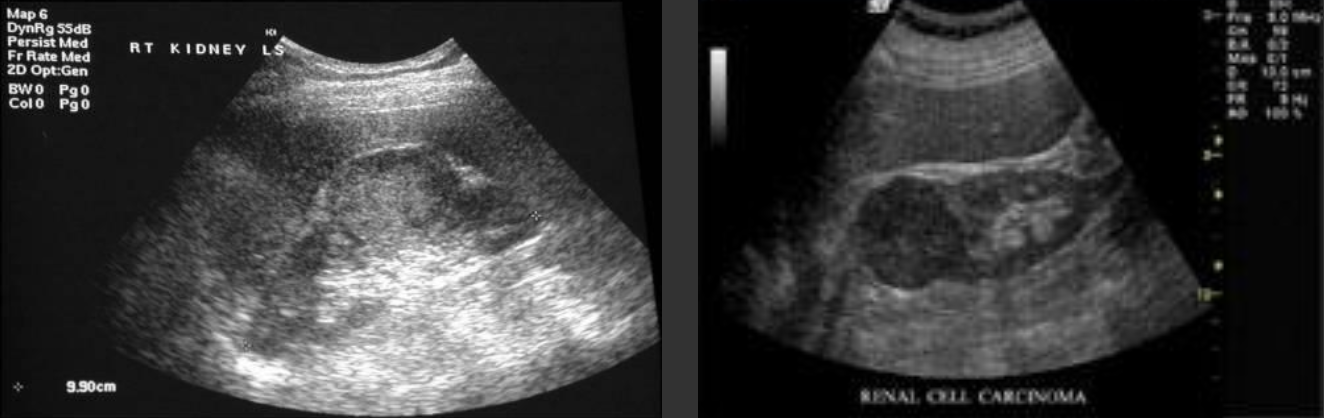

RCC (Renal Cell Carcinoma) → most common primary malignant tumor of the kidney

clinical hx: male, late middle age, smoking, ACDK, von Hippel Lindau, Tuberous sclerosis

s/sx: microscopic hematuria

2D US: solid, usually isoechoic but can vary, renal vein and IVC involvement, typically solitary and invades into surrounding vasculature

color doppler: vascular

DDX: AML, TCC